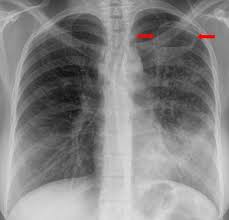

In this video, you'll learn how to identify when radiological pleura is abnormal and the key signs to look out for when trying to diagnose a pneumothorax. Check spelling or type a new query. When pneumothorax with its accompanying emphysema occurs as a complication of bronchoscopy, symptoms are usually severe, and require treatment. When a pneumothorax is clinically suspected, we routinely perform cxr on both inspiration (as per usual) and expiration. Agus suharto basuki, sp.p fakultas kedokteranuniversitas muhammadiyah surakarta 2011 2. Scarcely less important is the selection of the positionmost favorable for obtaining information in fluoroscopicand Special attention is paid to tension pneumothorax, to. A pneumothorax, légmell (ptx), az az életveszélyes akut kórállapot, amikor a mellhártya zsigeri és fali lemeze közé, azaz a mellhártyaüregbe levegő jut kívülről (a mellkasfal sérülésén át) vagy belülről (a tüdő vagy oesophagus folytonosságmegszakadása útján).

In this video, you'll learn how to identify when radiological pleura is abnormal and the key signs to look out for when trying to diagnose a pneumothorax. Ennek következtében súlyos respiratoricus állapotromlás következhet be, amely mielőbbi orvosi. Therefore, it is mandatory to treat it safely. Primärer spontanpneumothorax, es besteht keine gesicherte ursache und die betroffene person ist gesund. Tillståndet uppstår ofta spontant hos unga och friska utan känd lungsjukdom, men kan drabba alla åldrar med eller utan tydlig orsak Louis duringthepast fewyears, therehave been many importantadvances in the diagnostic method of thoracic conditions. We did not find results for: Patients with tension pneumothorax usually appear dyspnic and distressed. All 28 control roentgenograms were scored correctly. Cannot be detected even by the roentgen rays. Sekundärer spontanpneumothorax, wird durch lungenerkrankungen oder krankheiten anderer organe verursacht. Primær spontan pneumothorax (psp) opstår primært hos yngre (ofte under 45 år), lungeraske personer, og antages at skyldes bristning af subpleurale blærer/blebs. It entails few complications and little risk.

Pneumo, luft, och thorax, bröstkorg) är ett tillstånd då ena eller båda lungorna komprimeras till följd av luftansamling i lungsäcken. Hence, if one considered selective pneumothorax as a sign of pathology in. Temaet er også relevant for andre helsefagutdanninger. Chest (1977), 71, 211 bilateral spontaneous pneumothorax with pulmonary metastases from synovial cell sarcoma harjit singh, nachhattar singh and ravinderpal kaur government medical college and rajindra hospital, patiala, punjab, india summary the association of bilateral spontaneous pneumothorax with pulmonary metastases is rare. Røntgen af thorax viser en luftlomme med en synlig visceral pleuralinie (konveks mod brystvæggen), nogle gange foreligger der også lidt pleuravæske 1 ved en mindre pneumothorax (kappepneumothorax) er afstanden fra pleura viscerale (lungekanten) til indersiden af brystvæggen mindre end 2 cm thoraxrøntgen med forskellige typer af pneumothorax Cannot be detected even by the roentgen rays. It occurs through an immediate disruption of the visceral pleura that results in an accumulation of air in the pleural space. Ennek következtében súlyos respiratoricus állapotromlás következhet be, amely mielőbbi orvosi. Distinctive variability in forms of effusions and to special methods. Maybe you would like to learn more about one of these? It entails few complications and little risk. Sekundärer spontanpneumothorax, wird durch lungenerkrankungen oder krankheiten anderer organe verursacht. When a pneumothorax is clinically suspected, we routinely perform cxr on both inspiration (as per usual) and expiration.

Røntgen af thorax viser en luftlomme med en synlig visceral pleuralinie (konveks mod brystvæggen), nogle gange foreligger der også lidt pleuravæske 1 ved en mindre pneumothorax (kappepneumothorax) er afstanden fra pleura viscerale (lungekanten) til indersiden af brystvæggen mindre end 2 cm thoraxrøntgen med forskellige typer af pneumothorax pneumothorax. Røntgen af thorax viser en luftlomme med en synlig visceral pleuralinie (konveks mod brystvæggen), nogle gange foreligger der også lidt pleuravæske 1 ved en mindre pneumothorax (kappepneumothorax) er afstanden fra pleura viscerale (lungekanten) til indersiden af brystvæggen mindre end 2 cm thoraxrøntgen med forskellige typer af pneumothorax